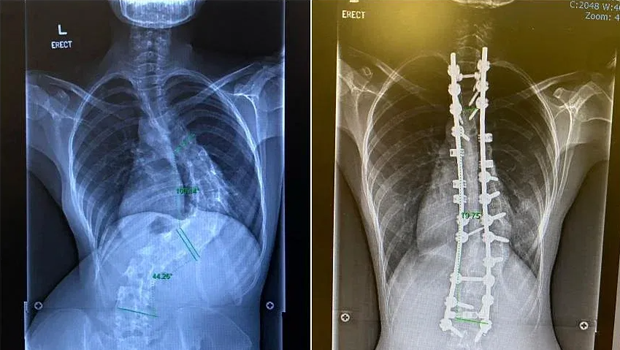

To correct severe scoliosis (left), Ms Natasha Ramli had to have two titanium rods and 20 screws implanted in her back (right). PHOTOS: NATASHA RAMLI

“I was diagnosed at age 11 during one of those health screenings in primary school, and I was referred to a specialist. He recommended that I wear a body brace to correct my spine. That did not work out well and I stopped wearing the brace,” she told ST. Her scoliosis became progressively worse, measuring 80 degrees 10 years later. Surgical intervention is usually needed when the curvature exceeds angles of 45 to 50 degrees.

“I suffered back pains, developed uneven hips and had trouble breathing. When the surgeon discovered how severe the curve was, I was told to go for surgery if I wanted a good quality life,” she said. She had two titanium rods and 20 screws implanted in her back.